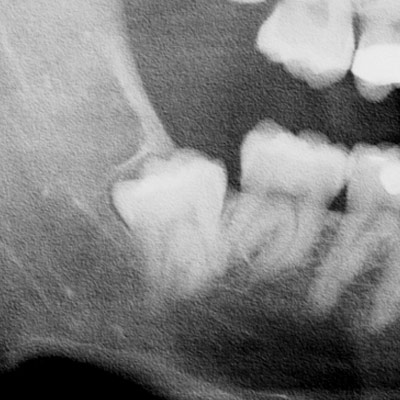

Percorso di chirurgia orale: Le basi della chirurgia orale

Come prepararti a gestire il trattamento chirurgico sui pazienti: dalla prima visita, attraverso una valutazione clinica pertinente, per mezzo di strumenti diagnostico-operativi idonei, alla prevenzione e gestione delle complicanze con l’obiettivo di ottenere risultati predicibili e stabili nel tempo.